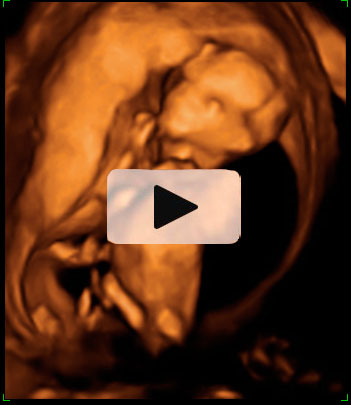

En la ecografía en 3D del feto en la 15ª semana de gestación se aprecia su anatomía. Es casi como la de un bebé a punto de nacer. Mide alrededor de los 10 cm y pesa unos 50 gramos.

Imagen de un feto de 15 semanas en ecografía 3D

La imagen es impresionante: la apariencia de este feto, de 15 semanas, es la de un niño que no le queda mucho tiempo de gestación para nacer. Cabeza, tronco, brazos y piernas se perfilan perfectamente en la ecografía del primer trimestre. Se lleva la mano a la boca mientras descansa apoyado en la pared uterina, como es normal es esta edad gestacional. La mayoría de las madres no se imagina que los fetos están tan "acabados" con apenas cuatro meses de embarazo.